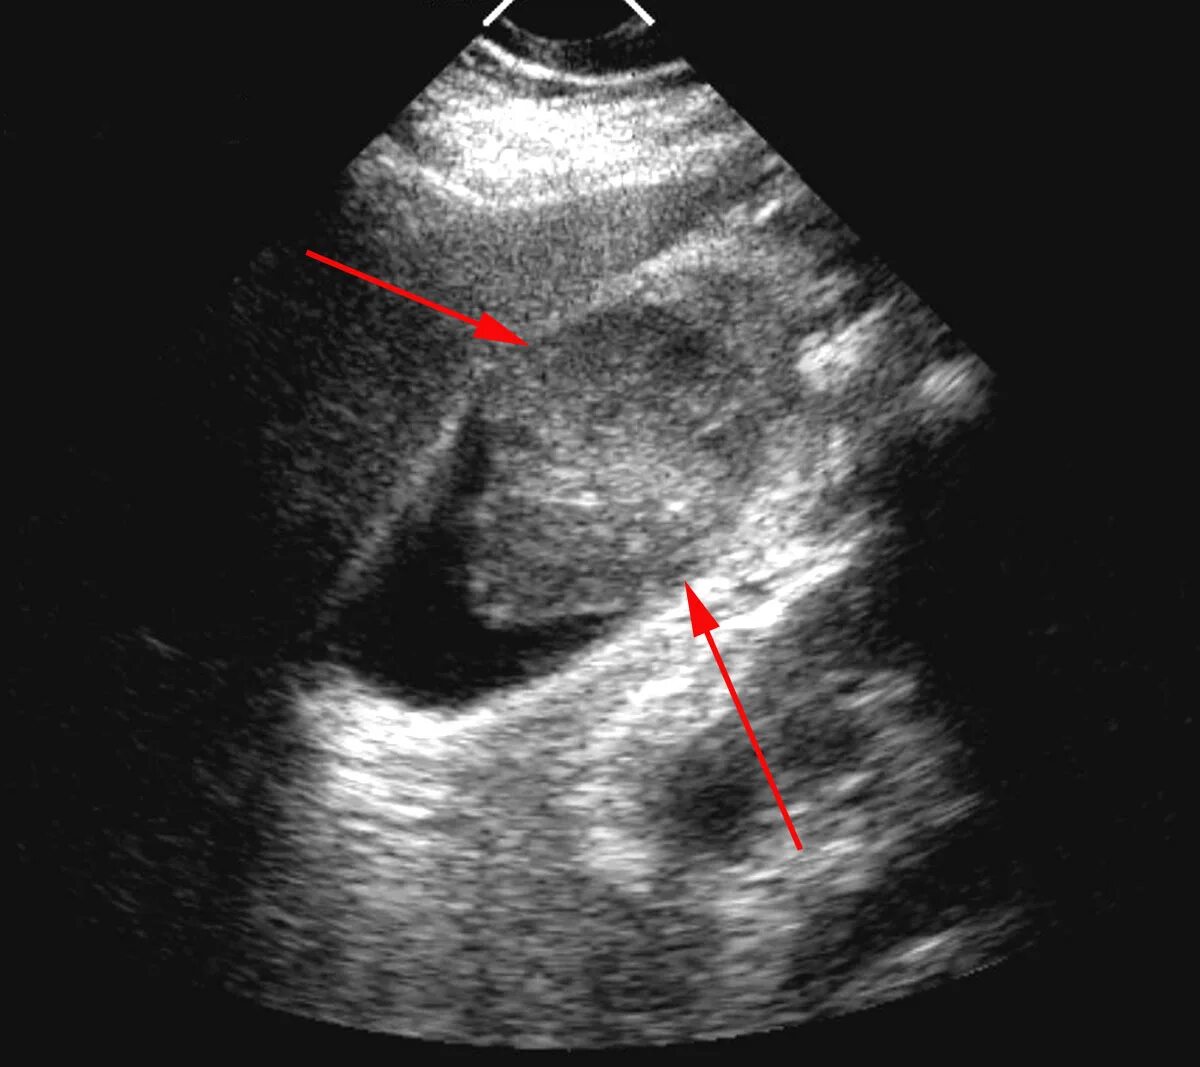

Метастазы в желчном